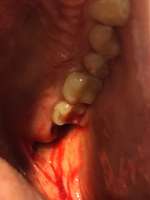

Как и обещал. Забавно, в зеркале кажется не так криво.

Боль на третий день похожа на второй день, спасаюсь болеутоляющим. Но целом уже привык.

Вчера делал панорамный снимок. Всё как >>513480 сказал, ортодонт взял его только посмотреть. Внимание, вопрос знатокам, ортодонт посмотрел на второй пикрелейтед и сказал, что зуб в котором штифт нужно переделывать - канал не полностью залечили, а так же второй зуб - там тоже проблема с каналом и что если ставить брекеты, то им обоим придет пизда. Когда это лечить не понятно, времени в обрез, завтра пойду к своему врачу который год-полтора назад мне эти зубы лечил, послушаю что скажет. В то, что она плохо сделала не хочется верить, но нужно быть реалистом.

Еще вопрос, сегодня пидорю зубы и вижу ДЫРУ, ЧЕРТОВУ ДЫРУ В ДЕСНЕ около места, из которого мне выпилили зуб мудрости. Еще вчера этой дырки не было, засунул туда ершик, дырка оказалась глубокая, вытащил оттуда петрушку, попутно отложив немало так кирпичей. Завтра побегу к хирургу. Всё это уже знатно так заебало, за лето потратил на брекеты, пломбы, снимки, лекарства и прочие операции больше 40к и конца этому не видно.